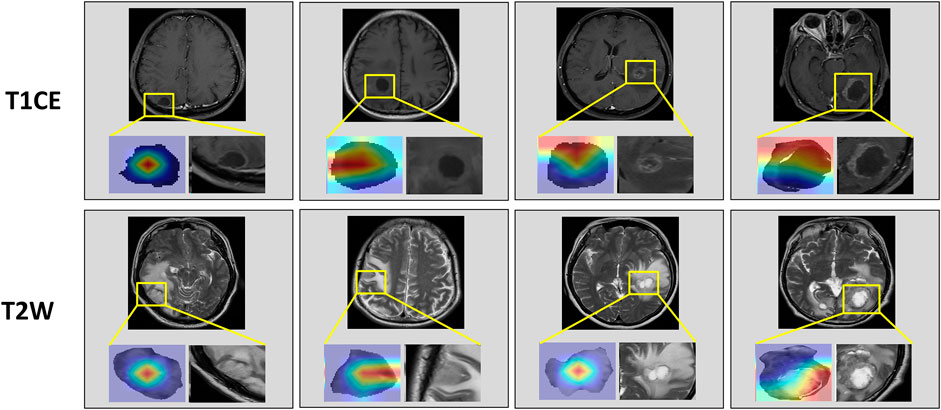

Table 2 compared the performance of the proposed EGFR-ModelNo Seg−VPE, EGFR-ModelNo VPE, EGFR-ModelNo Seg and EGFR-ModelSeg-VPE for predicting the EGFR mutation status. Without the subnetwork for segmentating the BM, the EGFR-ModelNo Seg−VPE yielded lower AUCs, accuracy, F1-score, precision, and recall compared with EGFR-ModelNo VPE in primary and external cohorts. The decreased predictive performance in EGFR-ModelNo Seg−VPE suggested the necessity of the segmentation subnetwork. By integrating VPE, the EGFR-ModelNo Seg showed better performance than EGFR-ModelNo Seg−VPE in terms of AUC, accuracy, F1-score, precision, and recall. This indicated that the VPE can provide additional information to improve the capability of predicting the EGFR mutation status. The EGFR-ModelSeg-VPE, integrating both VPE and segmentation subnetworks, performed the best among all models for predicting the EGFR mutation status. ROC curves of all models on primary and external sets were shown in Figure 4. As shown in Figure 5, the Grad-CAM heatmaps highlight high-response areas within the segmented tumor region, indicating that the prediction of EGFR mutation status is driven by biologically relevant features. These results illustrate a link between the model architecture, particularly the segmentation-guided feature extraction, and the spatial mapping of predictive regions.

Figure 5. Attention heatmaps on the brain metastasis (BM) visualized by Grad-CAM. The first row shows heatmaps in T1CE MRI. The second row shows heatmaps in T2W MRI.

To predict EGFR-TKI therapy response, we extracted DL features and handcrafted features from patients with EGFR mutation. The analysis of variance (ANOVA) and principal component analysis (PCA) (Witten et al., 2013) were applied to dimensionality reduction and screen features. Finally, we used a decision tree model to predict the response to EGFR-tyrosine TKI therapy. To enhance interpretability and reveal spatial correlations between image regions and prediction results, we applied Grad-CAM (Selvaraju et al., 2017) to the final convolutional layer of the DenseNet-121 classifier. This allowed us to visualize the discriminative regions that most influenced the EGFR mutation prediction. Since the classifier receives input features extracted from the segmented tumor region, the resulting attention maps reflect localized regions within the BM that are most relevant to the model’s decision-making process. In the training process, the model is optimally trained by adaptive moment estimation (Adam) (Kinga and Adam, 2015) with a learning rate of 0.0001; the epoch of the training model was set to 100. All DL experiments were performed in Python (v.3.6) using Keras (version 2.3) on a single GPU (Nvidia GeForce 3090) workstation.